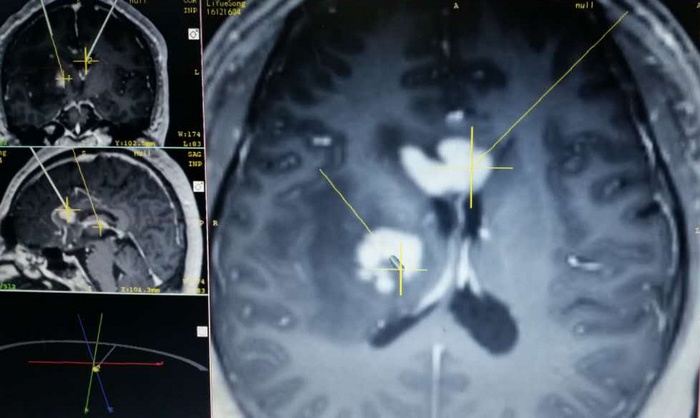

突如其来的疾病给王先生一家人带来了巨大的打击。几经辗转,王先生来到我院神经外科就诊,张洪兵主任与神经外科团队多名专家针对患者病情和影像学资料进行分析,考虑颅内病变为恶性淋巴瘤可能性大,经过认真讨论后制定了详细的疾病诊治方案,经过全身PET-CT检查后进一步证实颅内病灶为原发性。在排除手术禁忌后,张洪兵主任和邰军利副主任医师提出了立体定向病变活检是明确颅内多发病灶病理性质的最佳方式,但是患者颅内病灶毗邻重要血管和功能区,手术难度极大。神经外科团队迎难而上,在医学影像科的协助下为患者完善了术前影像评估及定位,将所获得的影像数据应用Leksel立体定向系统进行精确计算,并对病灶穿刺靶点及路径进行慎重选择和对比,最终确定了安全准确的活检穿刺入路。手术顺利,病理标本获得满意,最终病理确诊为中枢神经系统淋巴瘤。此后,王先生接受了化疗,一月的治疗完成后颅内病灶消失,左侧肢体可以做简单的活动,现在已完成了第三个疗程的化疗,基本恢复到发病前的状态,已经重新回归到社会和家庭。